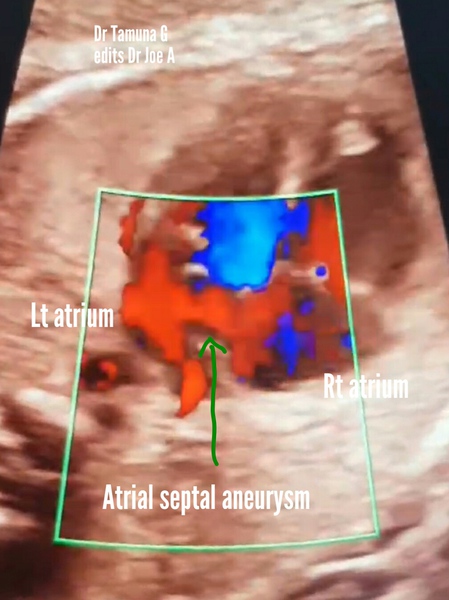

atrial-septal-aneurysm

This 30 week fetus fetal heart echocardiography (echo) video and images show:

= atrial septal aneurysm with bulging of the membrane covering the foramen ovale (a part of the septum primum of the interatrial septum)

= the membrane of the septum primum bulges from the interatrial septum into the left atrium due to pressure from the blood flowing from the right atrium across the foramen ovale

=diagnostic point: to be labelled atrial septal aneurysm- the membrane should bulge more than 50 % of the width of the left atrium

= other synonyms for atrial septal aneurysm: foramen ovale aneurysm, aneurysm of septum primum

= fetal left atrium is smaller than normal due to obstruction to flow (by atrial septal aneurysm) from Rt. atrium across foramen ovale.

= delayed complications include: cardiac arrythmias

= usually not associated with other cardiac anomalies

= atrial septal aneurysm usually disappears after boirth due to closure of the foramen ovale.

= the fetal ultrasound echo video of atrial septal aneurysm and images are courtesy of Dr. Tamuna G (edits by me, Dr. Joe A)